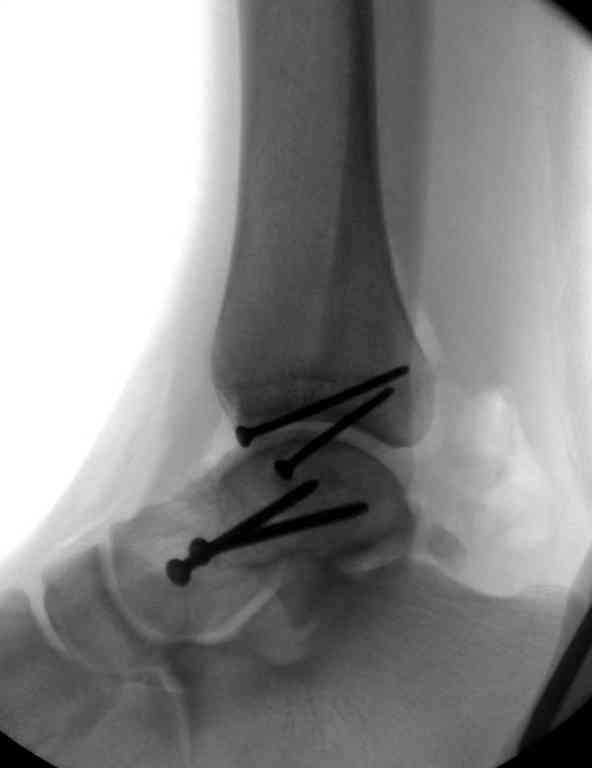

Переломовывих тарана с повреждением медиальной стороны. Через 4 часа после поступления проведена репозиция и фиксация тарана после Irrigation&Debridment. Частичное несращение медиальной лодыжки не беспокоит, вернулся к активному образу жизни. Полная нагрузка разрешена через 11 недель. Финальные снимки через 11 месяцев.